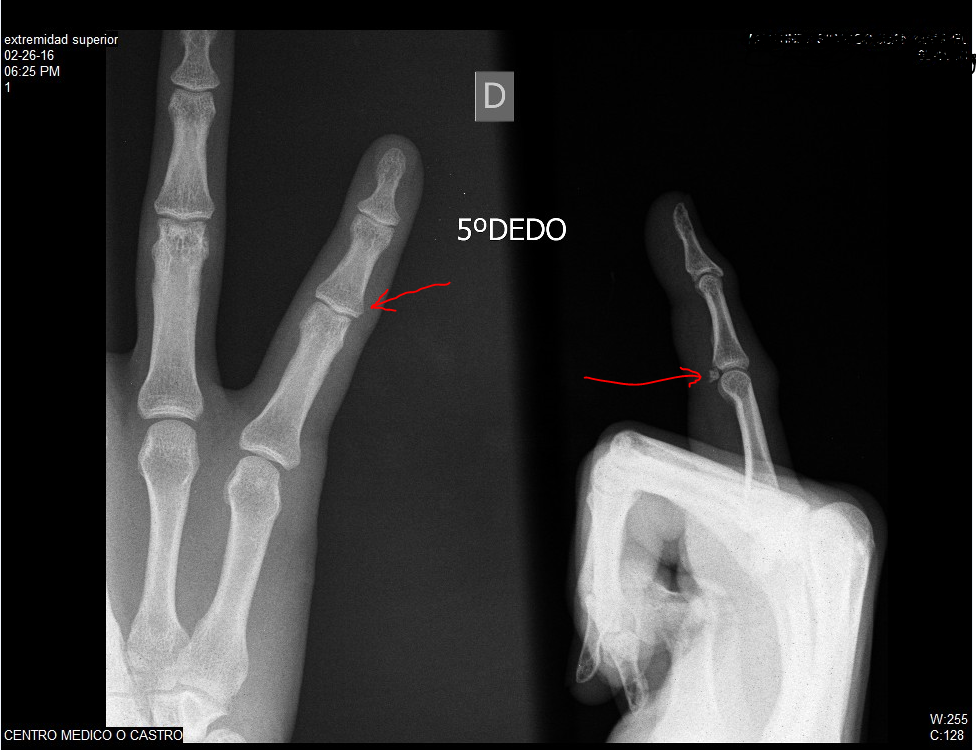

El esfenoides: Fractura de falange. 2 imágenes 1 caso.

Source: elesfenoides.blogspot.com 1600 x 1008